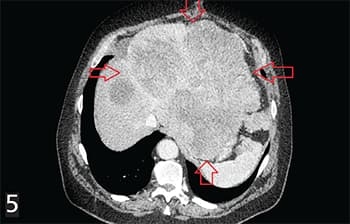

Рисунок 5. ГИСО верхней трети желудка. Состояние после секторальной резекции желудка. Прогрессирование: многоузловой опухолевый конгломерат с поражением печени, стенок желудка, 12-перстной кишки, левой ножки диафрагмы, брыжейки, сосудов с метастазами по брюшине, метастазами в мягких тканях передней брюшной стенки.В связи с этим рентгенологическое заключение и максимальное приближение к морфологической оценке на дооперационном этапе имеет большое значение в определении тактики ведения и лечения пациента.

Рисунок 5а. Тот же пациент, состояние после курсов МХТ иматинибом с положительной динамикой за счет редукции всех опухолевых очагов.Но, с другой стороны, для ГИСО отсутствуют какие-либо патогномоничные признаки, зачастую ее практически невозможно отличить от ряда других новообразований, таких как лейомиома ЖКТ, желудочно-кишечные лейомиосаркомы или лимфомы.